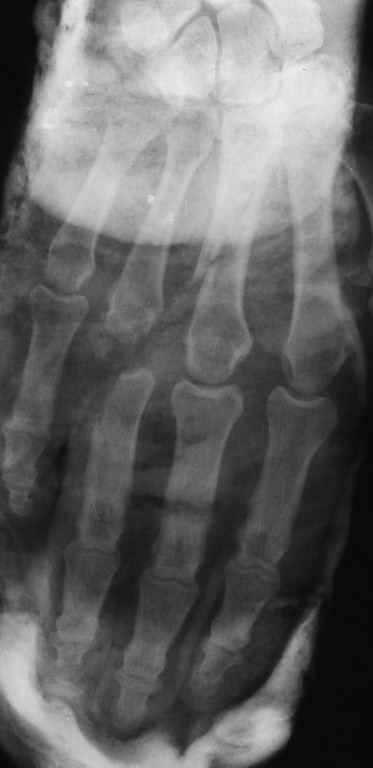

Диагноз: Стойкая Смешанная дермотеногенная контрактура 3,4 пальца правой кисти.

Судя по выписному эпикризу, рентгенограммам и фотографиям, пациенту

показано этапное лечение.